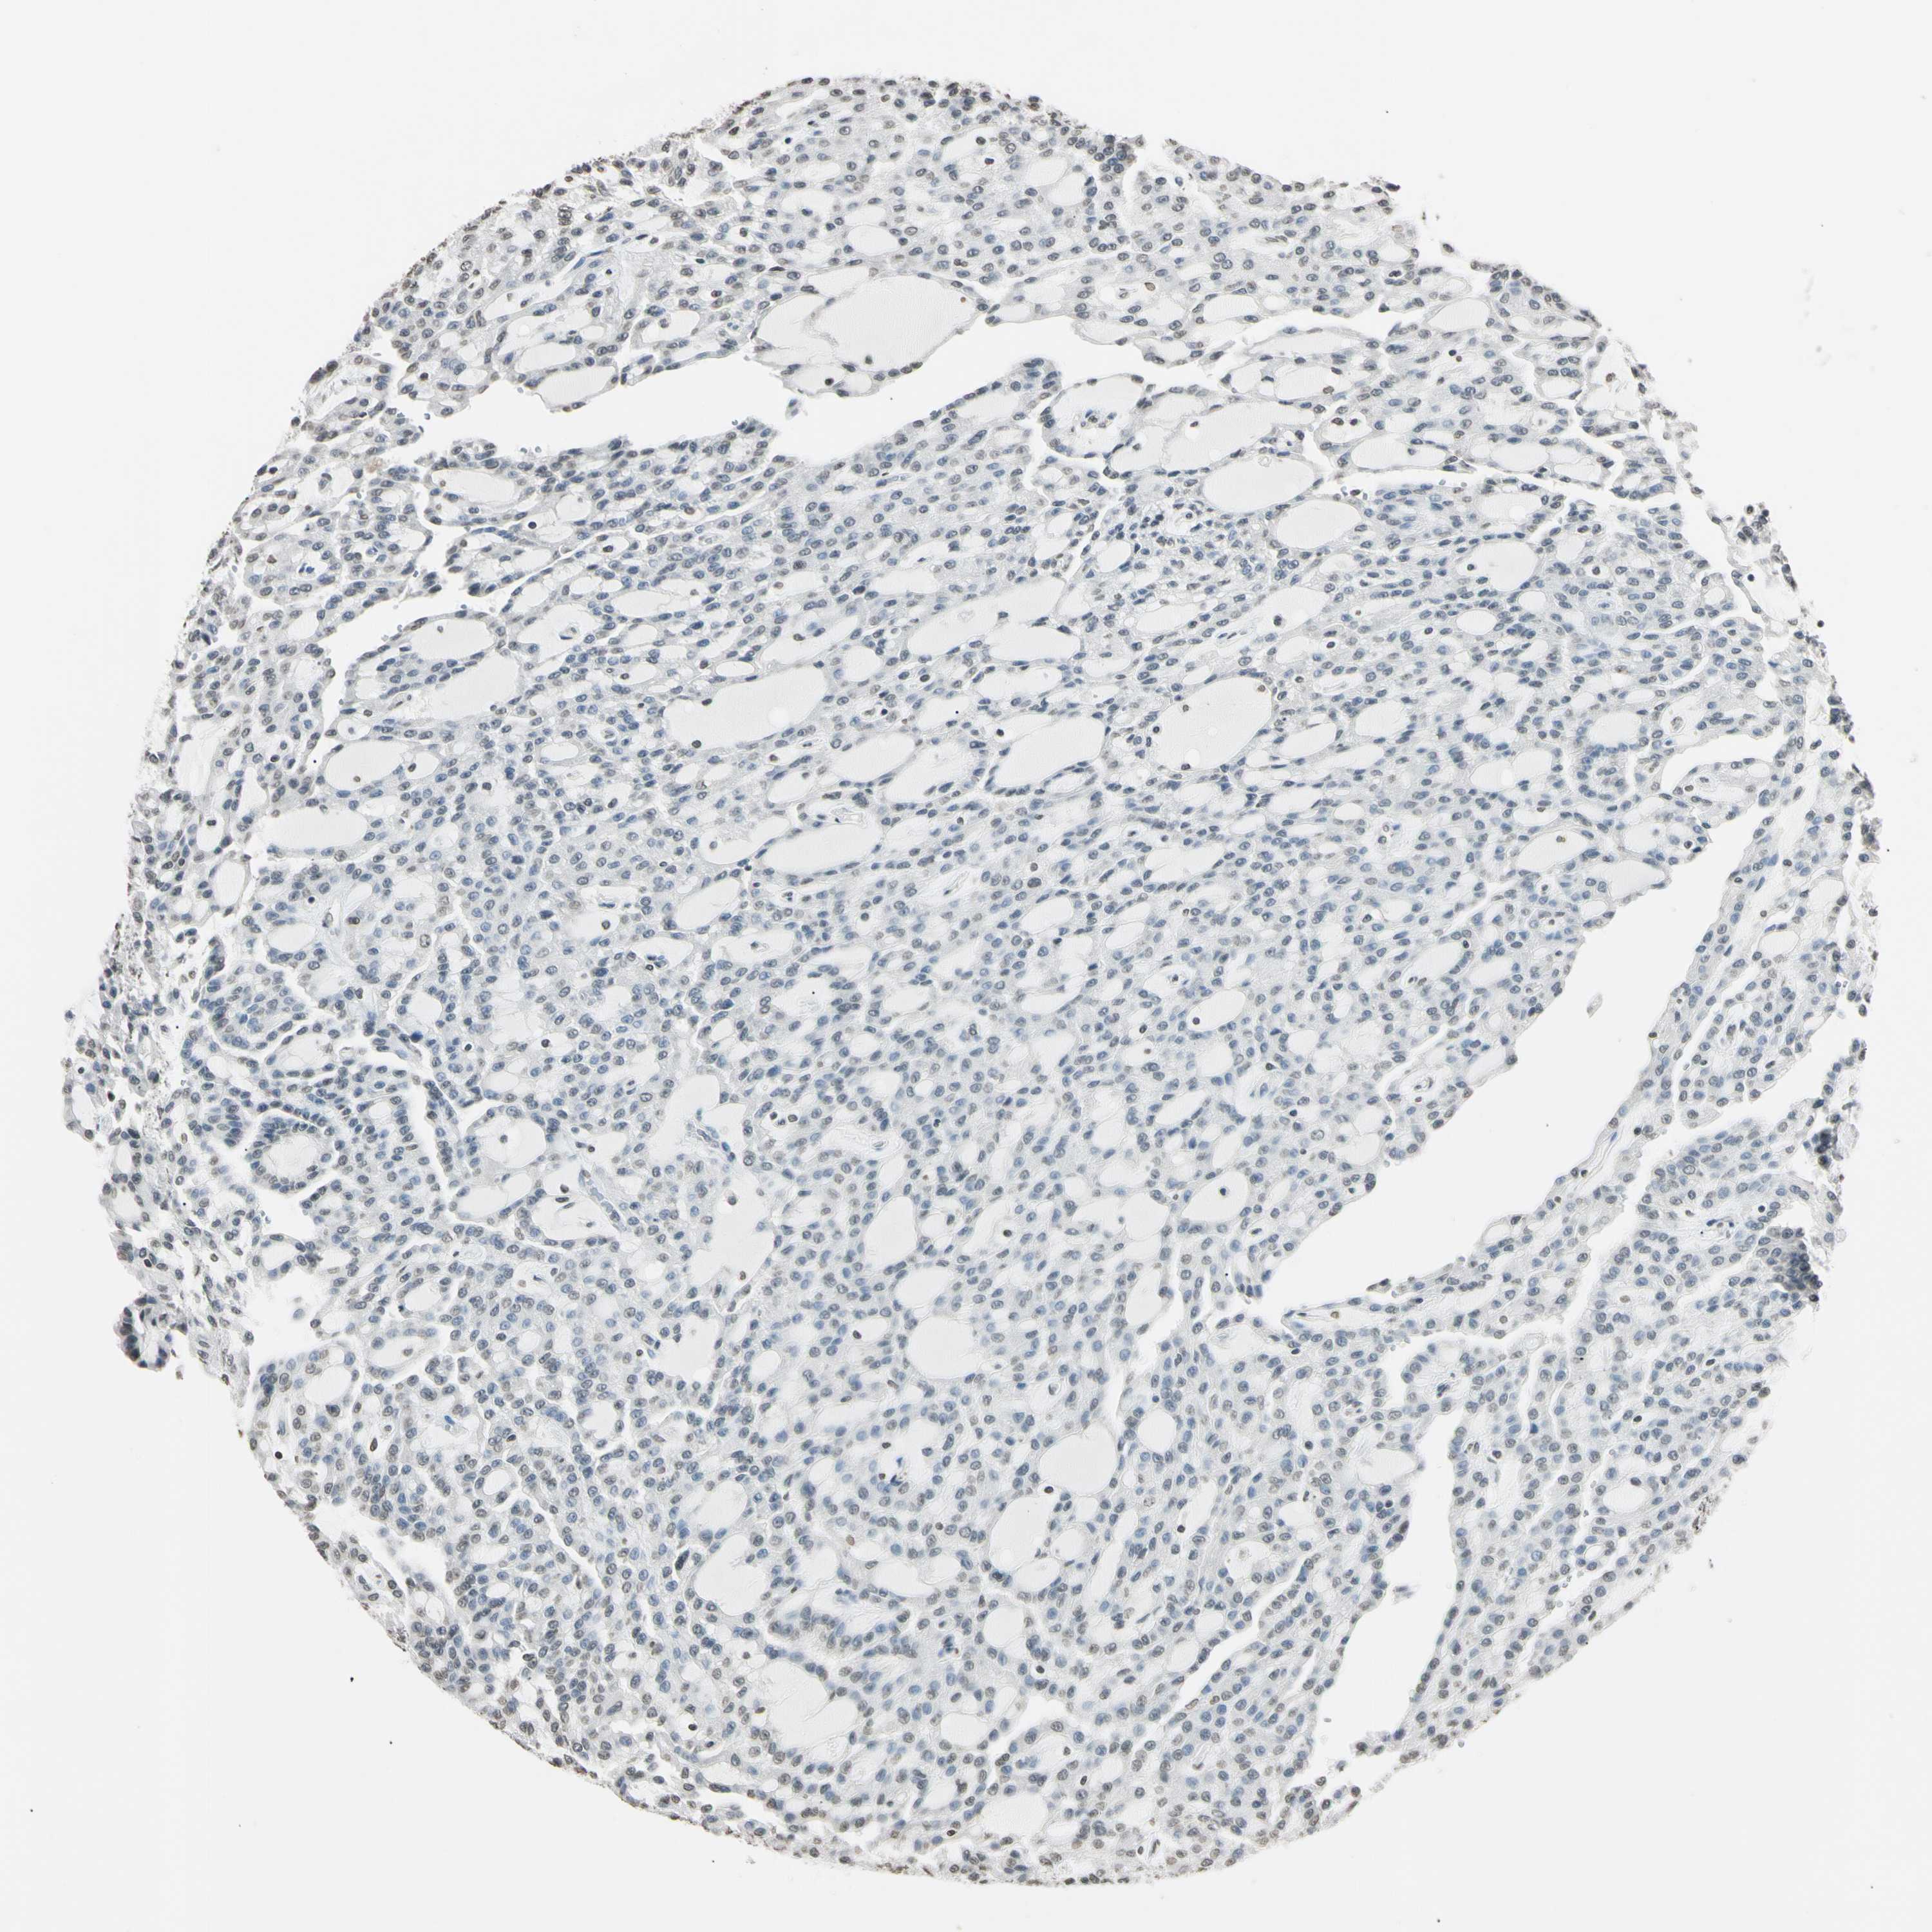

KIDNEY RENAL CLEAR CELL CARCINOMA (VALIDATION) - Interactive survival scatter ploti

The Survival Scatter plot shows the clinical status (i.e. dead or alive) for all individuals in the patient cohort, based on the same data that underlies the corresponding Kaplan-Meier plots. Patients that are alive at last time for follow-up are shown in blue and patients who have died during the study are shown in red.

The x-axis shows the expression levels (FPKM) of the investigated gene in the tumor tissue at the time of diagnosis. The y-axis shows the follow-up time after diagnosis (years). Both axes are complimented with kernel density curves demonstrating the data density over the axes. The top density plot shows the expression levels (FPKM) distribution among dead (red) and alive patients (blue). The right density plot shows the data density of the survived years of dead patients with high and low expression levels respectively, stratified using the cutoff indicated by the vertical dashed line through the Survival Scatter plot. This cutoff is automatically defined based on the FPKM cutoff that minimizes the p-score. The cutoff can be changed by dragging the vertical line or by entering a cutoff value in the square labeled "Current cut-off".

Under the Survival Scatter plot the p-score landscape (black curve; left axis) is shown together with dead median separation (red curve; right axis). Dead median separation is the difference in median mRNA expression between patients who have died with high and low expression, respectively. It is calculated as follows: median FPKM expression of dead patients with high expression - median FPKM expression of dead patients with low expression. This is intended to aid the user in visually exploring custom cutoffs and the associated p-scores and dead median separation.

Individual patient data is displayed and can be filtered by clicking on one or more of the category buttons on the top of the page. Categories describing expression level and patient information include: high, low, alive, dead, female, male and tumor stages. The scale of the x-axis can be toggled between linear and log-scale by clicking on the "x log" button. Mouse-over function shows TCGA ID, patient information and mRNA expression (FPKM) for each patient.

& Survival analysisi

Kaplan-Meier plots summarize results from analysis of correlation between mRNA expression level and patient survival. Patients were divided based on level of expression into one of the two groups "low" (under cut off) or "high" (over cut off). X-axis shows time for survival (years) and y-axis shows the probability of survival, where 1.0 corresponds to 100 percent.

CDC45 is validated prognostic, high expression is unfavorable in Kidney Renal Clear Cell Carcinoma (validation)

: 3.03

Average pTPM 2.3

Number of samples 100